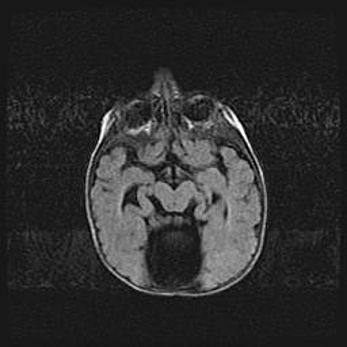

Открытая гидроцефалия.

Возраст: 6 месяцев 15 дней

Вес: 6200 г

Пол: женский

Окружность головы: 41 см

Срок гестации: 38 недель

Гидроцефалия головного мозга у новорожденных – это скопление избыточного количества цереброспинальной жидкости в головном мозге. Ее избыточное скопление в мозге приводит к патологическому расширению желудочков мозга (четырех полостей, расположенных в глубине белого вещества мозга, заполненных цереброспинальной жидкостью и связанных узкими проходами).

Открытый тип гидроцефалии (сообщающаяся) наблюдается тогда, когда нарушен механизм всасывания ликвора в системный кровоток. При этом типе причиной заболевания чаще всего является перенесенные ранее инфекции (например: менингит),  либо же наличие крови в субарахноидальном пространстве.